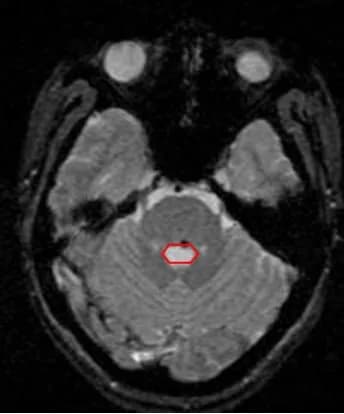

Xuất huyếtdị dạng mạch máuu máu thể hangtăng áp lực nội sọđộng kinh

U máu thể hang: Một dị dạng mạch não

U Máu Thể Hang: Tổng Quan và Điều Trị

Bệnh lý dị dạng mạch máu là sự xuất hiện một tổ chức mạch máu hoặc tổn thương bất ...